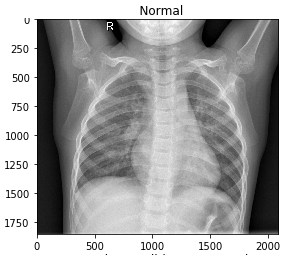

An Online Automatic Corona Diagnose System Based on Chest X-ray Images

This is a detailed paper for my online COVID-19 diagnosis system. Abstract. An outbreak of SARS-CoV-2 shocked healthcare systems around the world. It began in December 2019 in Wuhan, China, and spread out in over 120 countries in less than three months. Imaging technologies helped in COVID-19 fast and reliable diagnosis. CT-Scan and X-ray imaging…

Online COVID-19 detector based on CXR

It would be an honor to introduce this system which is available IN THIS LINK.

COVID-19 Detection with ML and CXR | تشخیص کرونا توسط یادگیری ماشین و CXR